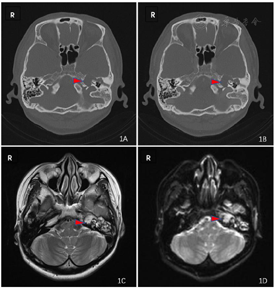

细菌培养、药敏(中耳拭子):铜绿假单胞菌(++);影像学检查结果如图1所示,颞骨薄扫CT(冠位+轴位)示:左侧岩骨次全切除术后改变,术腔内可见软组织密度影,中耳内听骨链显示欠清楚。第一次术前颞骨平扫MRI(DWI)示:左侧中耳乳突、颞骨岩部多发长T2信号团片状影,DWI高信号,ADC值减低,病变包绕左侧耳蜗、半规管、内听道,伴有内听道骨质及后颅窝骨质破坏。颞骨MRI平扫:T2高信号,DWI高信号,符合胆脂瘤影像学表现,根据病变位置及范围,可将其分为广泛型岩尖胆脂瘤。

岩尖胆脂瘤合并感染(左):该患者临床表现为长期间断流脓,伴有耳痛,体检可见:黄绿色黏稠分泌物。颞骨CT及MRI(DWI)平扫示:内听道及后颅窝骨质破坏,左侧中耳乳突、颞骨岩部多发长T2信号团片状影,DWI高信号,ADC值减低。中耳拭子细菌培养示绿脓杆菌(++)。综合患者病史,以及目前体检、辅助检查结果,诊断"岩尖胆脂瘤合并感染(左)"较为明确。